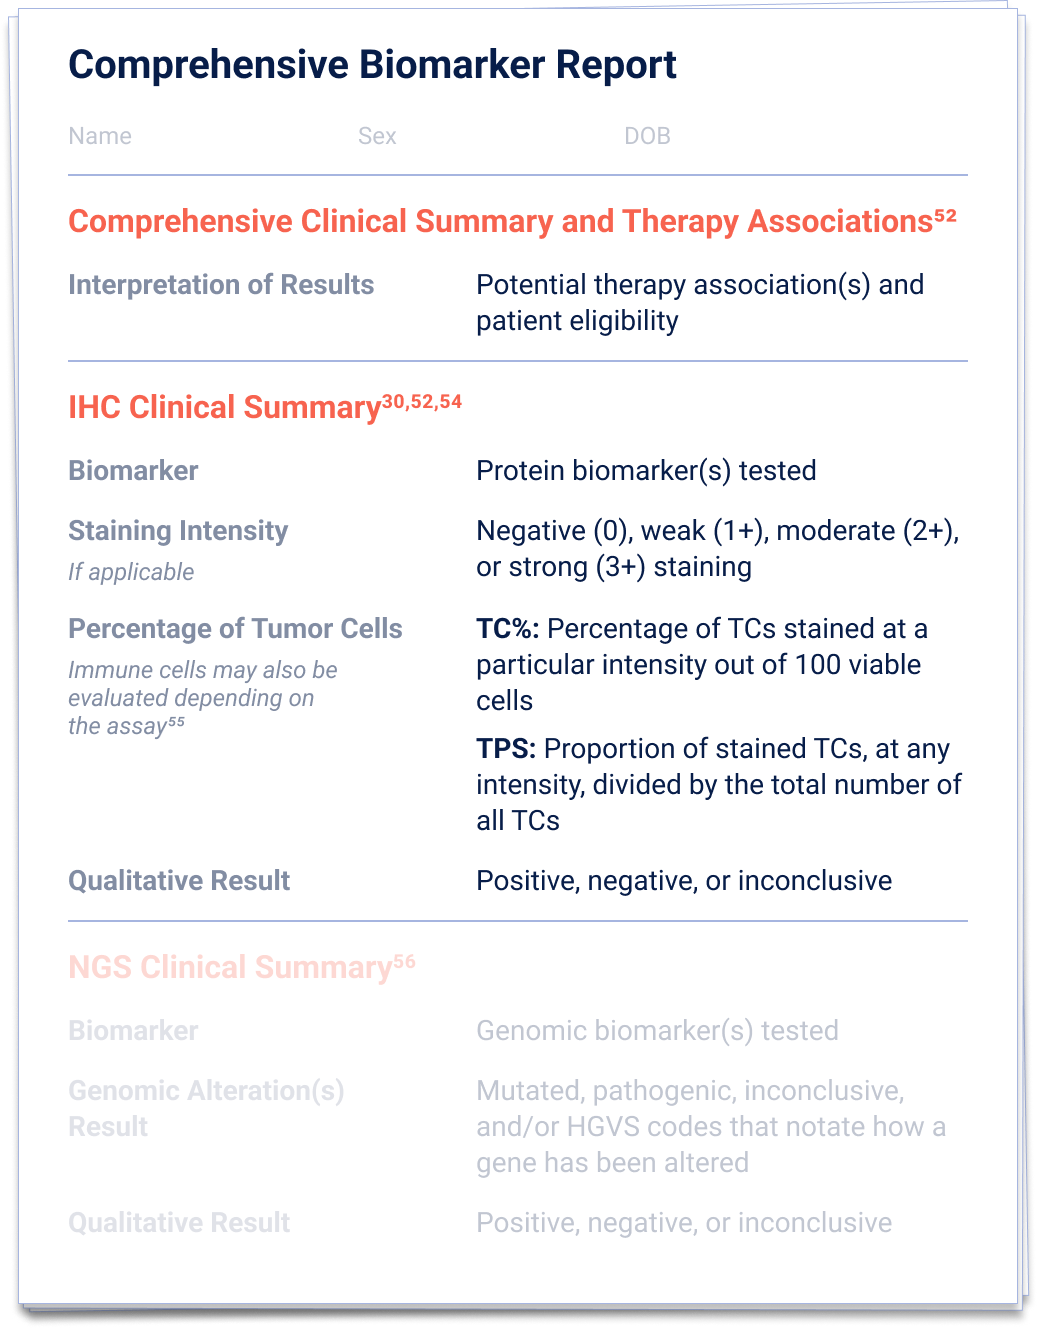

52. Penault-Llorca F, et al.

Virchows Arch. 2022;481(3):351-366.

54. Baskovich B, et al.

Arch Pathol Lab Med. 2024;148(10)1105-1109.